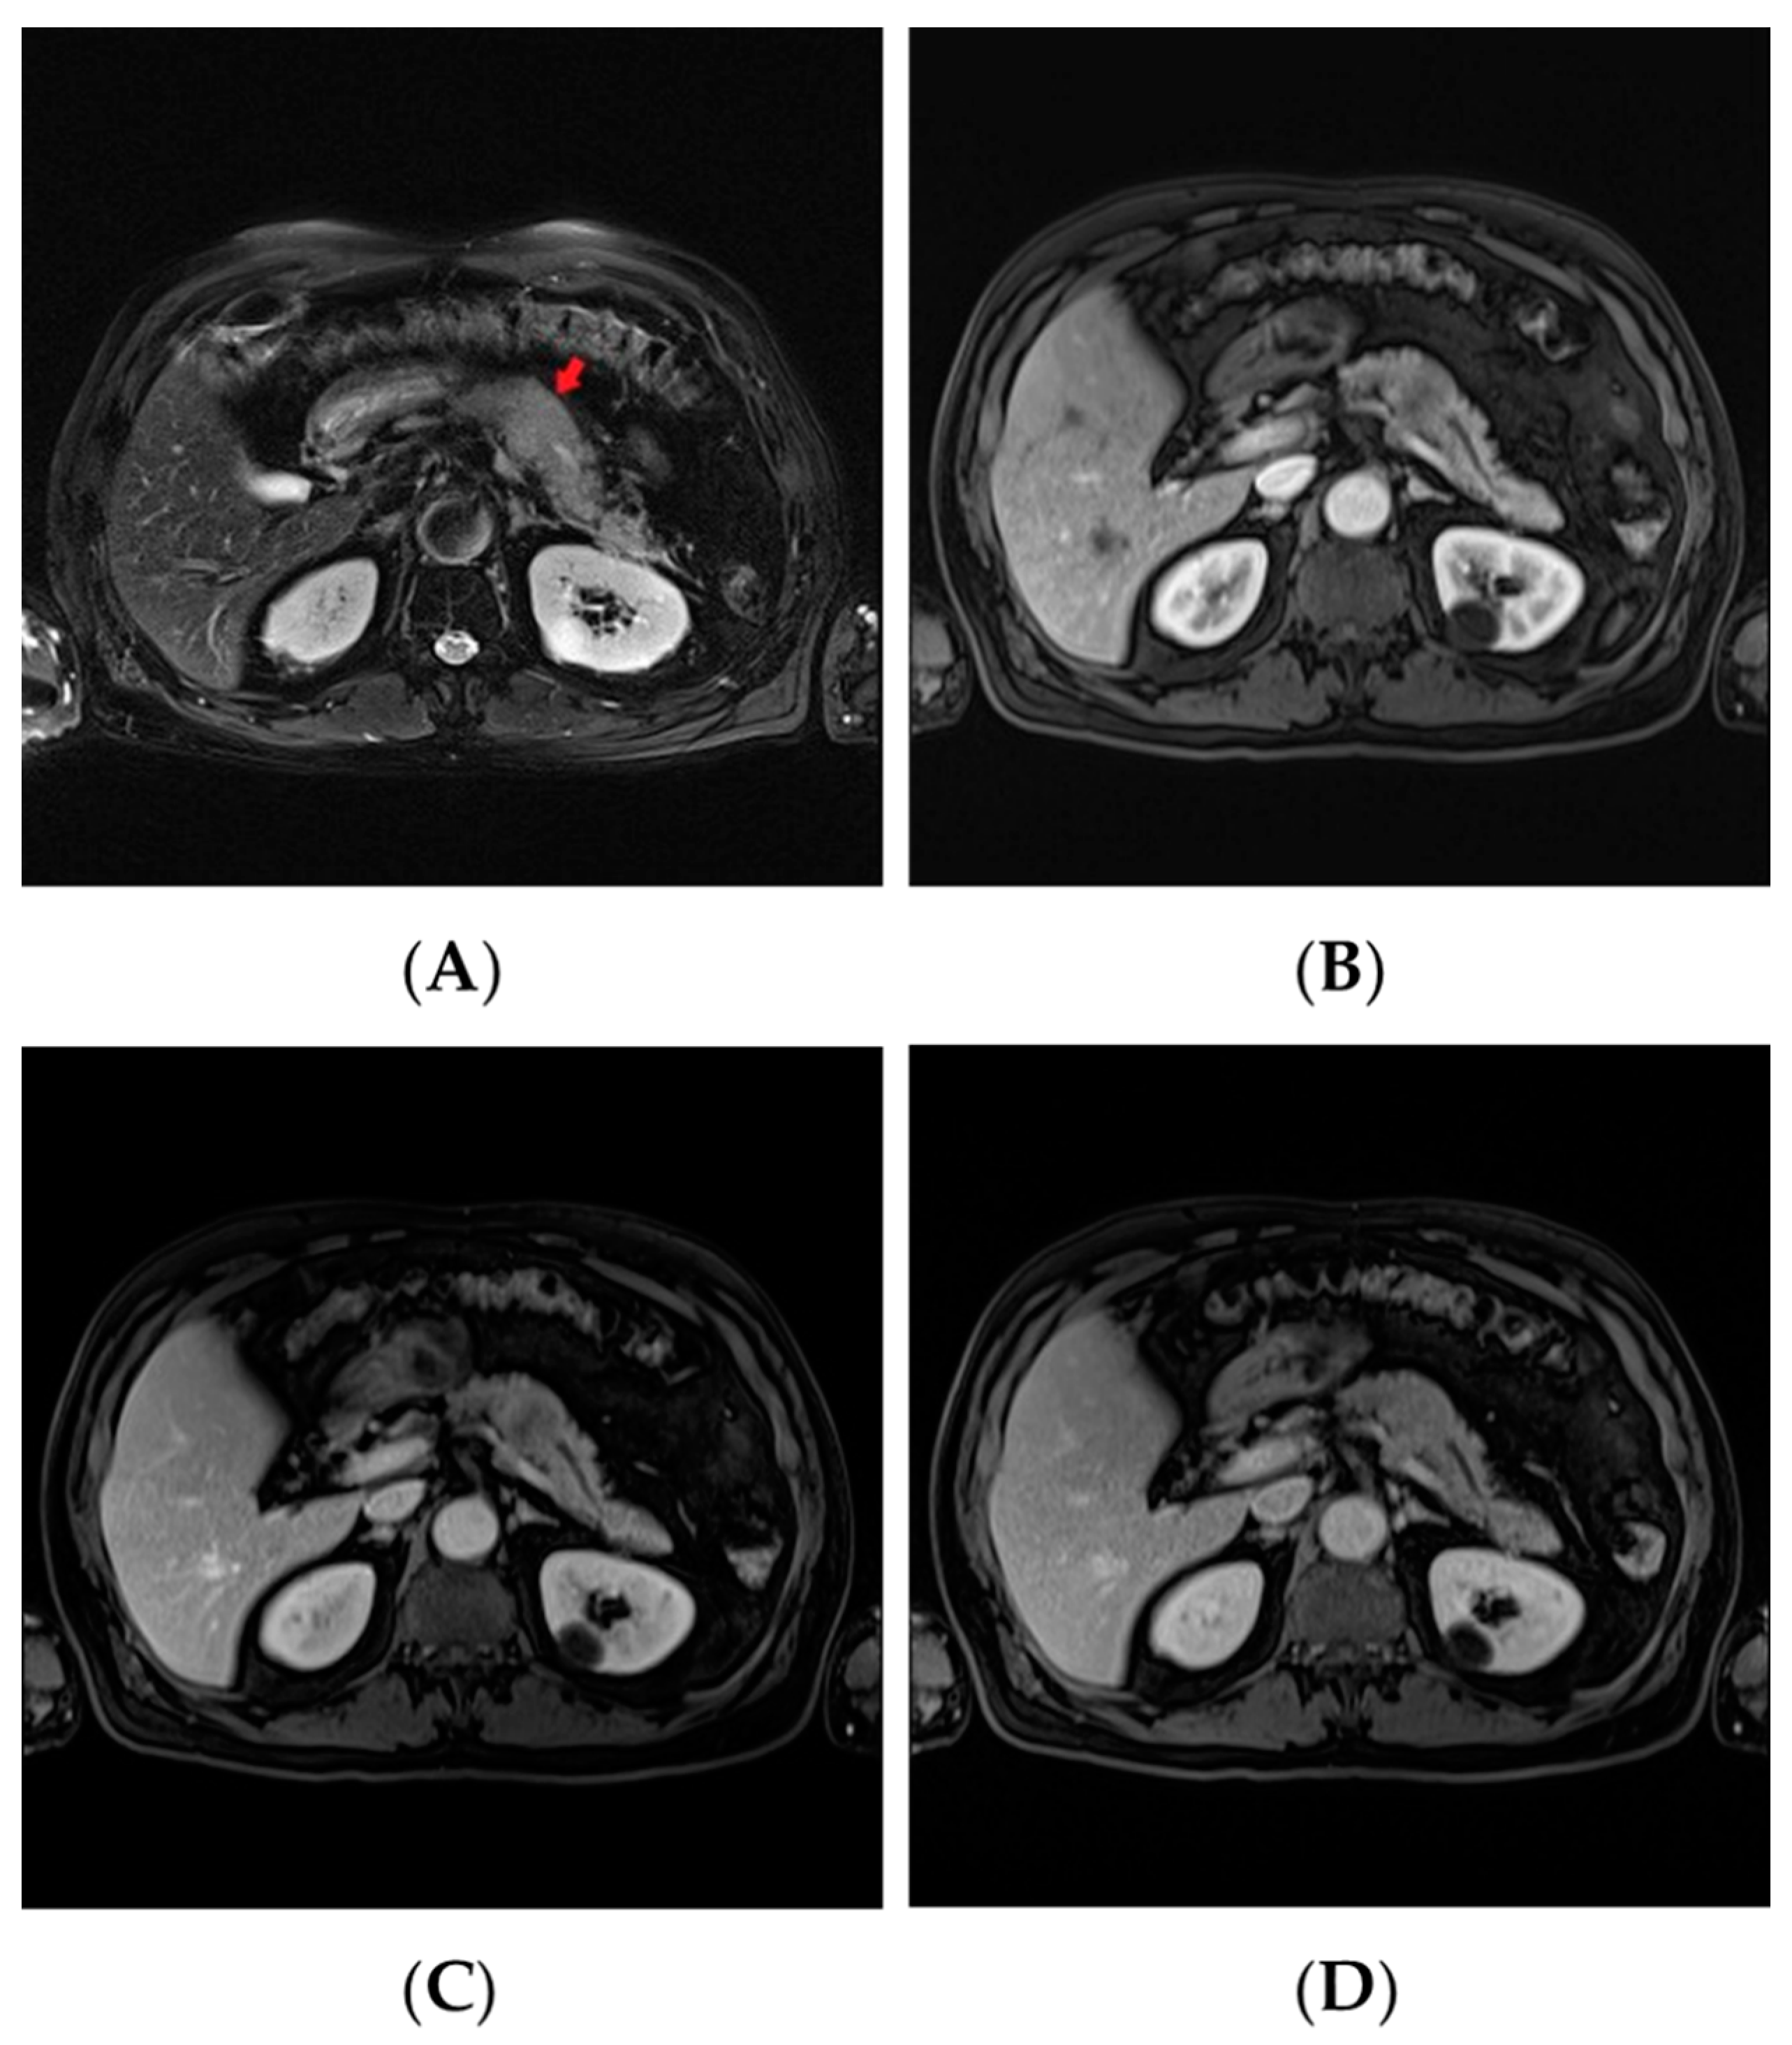

2. Case Report